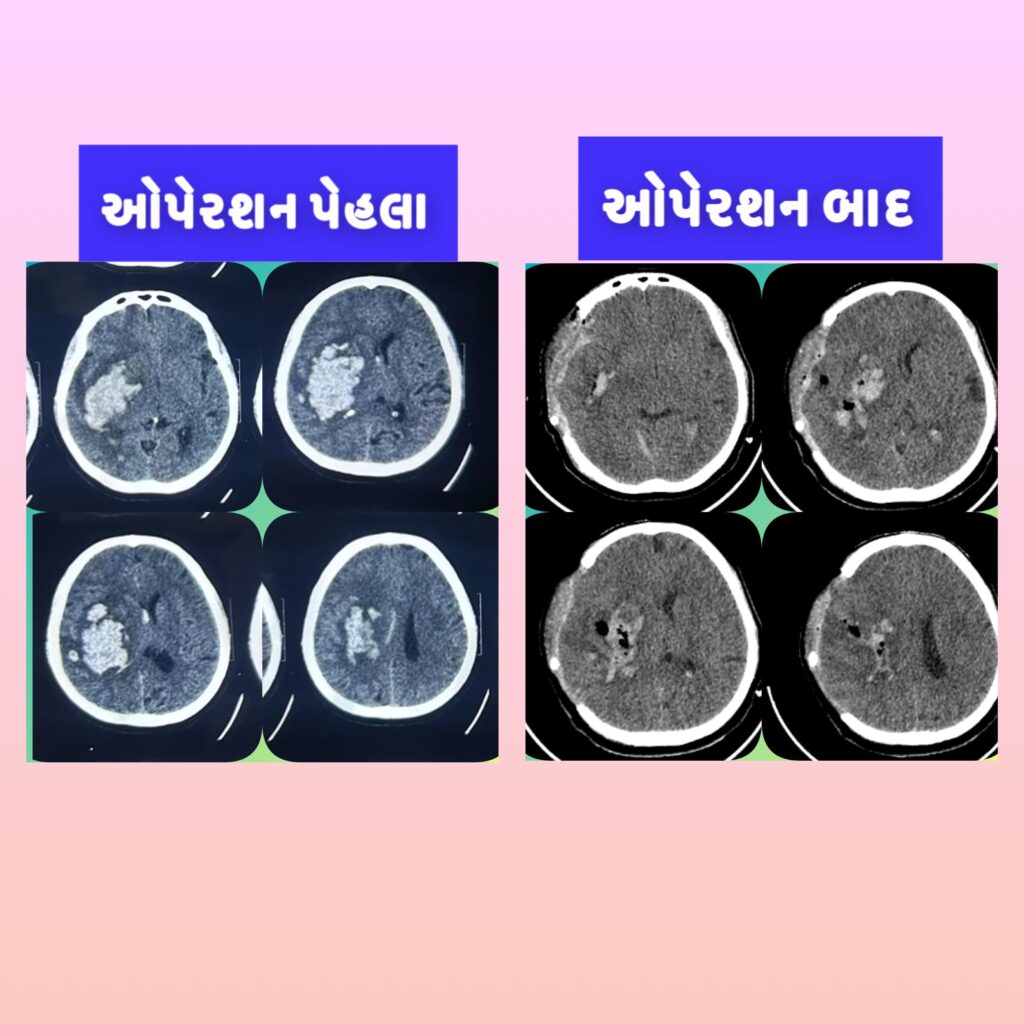

Dr. Ridham Khanderia, MBBS, MS (General Surgery), MCh (Neurosurgery) is a Neuro and Spine Surgeon with over 4 years of clinical experience and more than 2,000 neurosurgical and spine procedures performed. He completed his MBBS from PDU Medical College, MS in General Surgery from MP Shah Medical College, and MCh in Neurosurgery from AIIMS Rishikesh. He also holds a Fellowship in Endoscopic Spine Surgery from Pune.

He specializes in back pain, slip disc, sciatica, and complex spine and brain disorders, with a strong focus on conservative treatment, minimally invasive surgery, and ethical, patient-centered care.